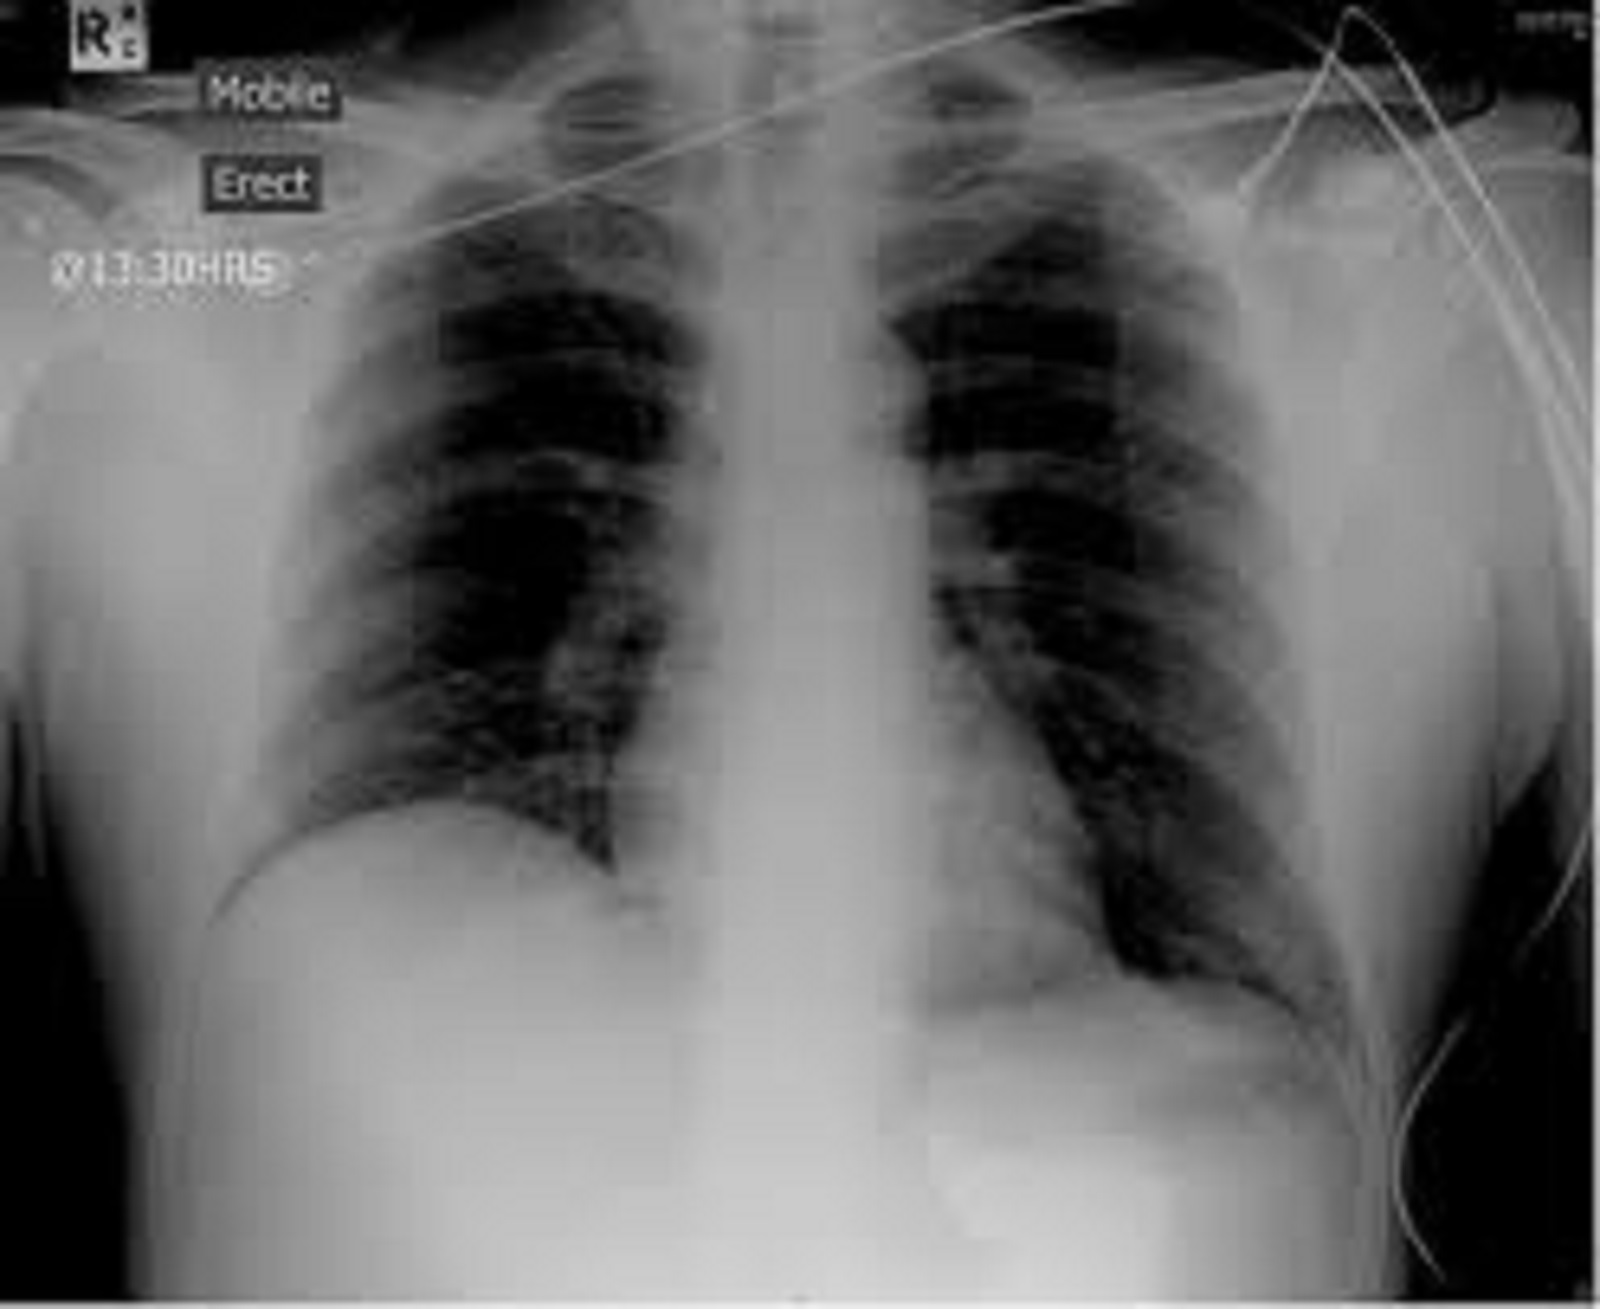

Dr Ivković je opisao svoje iskustvo Foto: Goran Srdanov/Nova.rs/Privatna arhiva Dr Ivković je opisao svoje iskustvo Foto: Goran Srdanov/Nova.rs/Privatna arhiva Dr Ivković je opisao svoje iskustvo Foto: Goran Srdanov/Nova.rs/Privatna arhiva Dr Ivković raskrinkava novu opasnu zaveru o koroni autor: Božica Luković Zdravlje 23. sep. 2021. 21:49 > 23. sep. 2021. 22:00 0 Podeli vest: Radiolog dr Aleksandar Ivković iz Niša od početka pandemije trudi se da pruži adekvatna objašnjenja za sve nedoumice koje prate koronavirus. Takođe, primerima iz svoje prakse bori se protiv mnogobrojnih teorija zavere koje unose dodatnu zabunu - a poslednja takva tvrdnja je da je virus SARS-CoV-2 zapravo arsenik. Podeli vest: Oglas Objavu dr Ivkovića prenosimo s njegovog bloga "Ljudi i ostale laži" u celosti."Zamolili su me da prokomentarišem tvrdnje prozarazaša da se ne radi o virusnoj infekciji SARS-CoV-2 već o masivnom i stalnom trovanju arsenikom. I pored ogromne želje da se valjam po podu držeći se za stomak od napada smeha, ipak ću napisati kako bi izgledalo kada bi neko trovao čitav svet, već skoro dve godine, arsenikom.Arsenik As je metaloid koji dolazi u četiri izotopa. Zanimljivo je da je neophodan za život u manjim količinama jer se nalazi u nekim enzimima. Toksičan je As2O3 dok postoje soli koje nisu toksične u nalaze se i nekim pesticidima. Poznati je bakteriostatik i nekada se koristio za lečenje sifilisa.Ako se udahne veća količina arsenika a to tvrde tvorci ove nove teorije dolazi do: vrtoglavice, glavobolje, konfuzije i teškog proliva.Prvo što se oseti je sledeće: metalni ukus u ustima i zadah na beli luk, ogromno lučenje pljuvačke, nemogućnost gutanja, krv u urinu, grčevi, gubitak kose, grčevi u stomaku, konvulzije (slično epi napadu), prekomerno znojenje, mučnina, povraćanje...Obavezno dolazi do promena na koži, posebno na koži prstiju, postaje tamno crvena. Sledeće strada jetra, nakon toga pluća pa bubrezi. Na kraju koma i smrt. Pluća kod akutnog trovanja arsenikomFoto: Aleksandar Ivković | Pluća kod akutnog trovanja arsenikomFoto: Aleksandar Ivković Pluća kod kovida-19Foto: Aleksandar Ivković | Pluća kod kovida-19Foto: Aleksandar Ivković Posledica dugog izlaganja su karcinomi, obično mokraćne bešike i leukemije.Simptomi nastaju brzo, u roku od 30 minuta. Odnosno nema nikakve sličnosti sa kovidom.Promene vidljive na plućima nastaju ako se arsenik pije. Slične su kao promene kod pušača i treba puno vremena da se razviju, godine. Kovid promene se razvijaju u 4 faze u roku od 15 danaNakon vlažnih snova prozarazaša vraćamo se u realan svet. Prosto ne znam da li je iko mogao da smisli luđu teoriju od ove. Zamislimo šta bi se desilo kada bi stvarno neko bacao arsenik sa neba i njime trovao ljude. Stradale bi sve biljke i životinje a prvo bi stradala deca.Sasvim suprotno od onoga što se događa. Prozarazaši obožavaju da lažu, da falsifikuju, da izmišljaju. Više ni ne pokušavaju da smisle nešto logično, sada su im teorije na granici komedije ali zato im bezobrazluk raste.Zamislite tek tvrdnje da je eto nekoliko ljudi umrlo iako su vakcinisani, mada jedan od njih nije ni vakcinisan. To im je dokaz da ne treba da se vakciniše a onih 30.000 mrtvih nevakcinisanih nisu dokaz. Ili sulude tvrdnje da je Indija najbolji primer kako ivermektin radi a procena umrlih u Indiji tokom naleta delte je čak do 4.7 miliona ljudi. Ako je neko lud da im poveruje", piše dr Ivković.***Bonus video:Pazite da ne preterate - Trovanje alkoholom Oglas video-cdn src="https://best-vod.umn.cdn.united.cloud/stream?asset=sortitrovanjealkoholomds-novas-worldwide&stream=hp1400&t=0&player=m3u8v&sp=novas&u=novas&p=n0v43!23t001"]Pratite nas i na društvenim mrežama:FacebookTwitterInstagram arsenik dr Aleksandar Ivković koronavirus kovid-19 teorija zavere Pratite nas na društvenim mrežama: Koje je tvoje mišljenje o ovoj temi? Učestvuj u diskusiji ili pročitaj komentare Budite prvi koji će ostaviti komentar Pošalji komentar Pročitaj komentare (0)